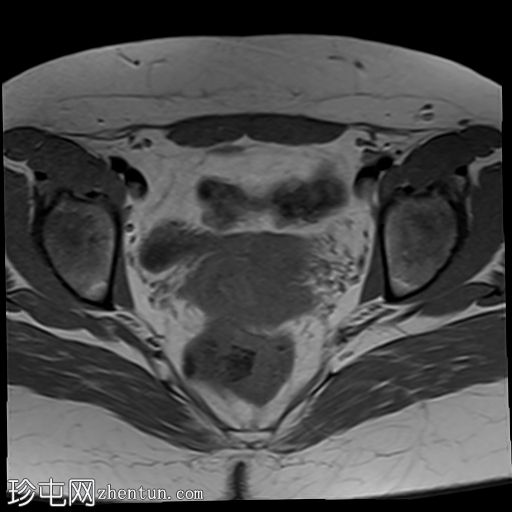

轴位

T2加权像

双侧卵巢位置接近(卵巢相吻),左侧卵巢内可见一边界清晰的囊性病变,大小约3.1 × 2.7 × 2.9 cm,T1加权像呈高信号,T2加权像可见暗点征及内部暗点征。以上MRI特征符合卵巢子宫内膜异位囊肿的诊断。

右侧卵巢可见一囊肿,大小约为 2.8 × 2.0 × 2.2 cm,T1 加权像呈高信号,囊内可见液-液平面,提示囊内含有不同时期的出血性物质。由于对侧卵巢存在典型的子宫内膜异位囊肿,且该囊肿无强化,影像学表现强烈提示为另一子宫内膜异位囊肿。

双侧卵巢均可见多个小卵泡。

子宫大小、轮廓及信号强度均正常,子宫内膜分区结构完整。未见局灶性肌层病变,子宫内膜厚度在正常范围内。

左侧盆腔可见少量游离液体。